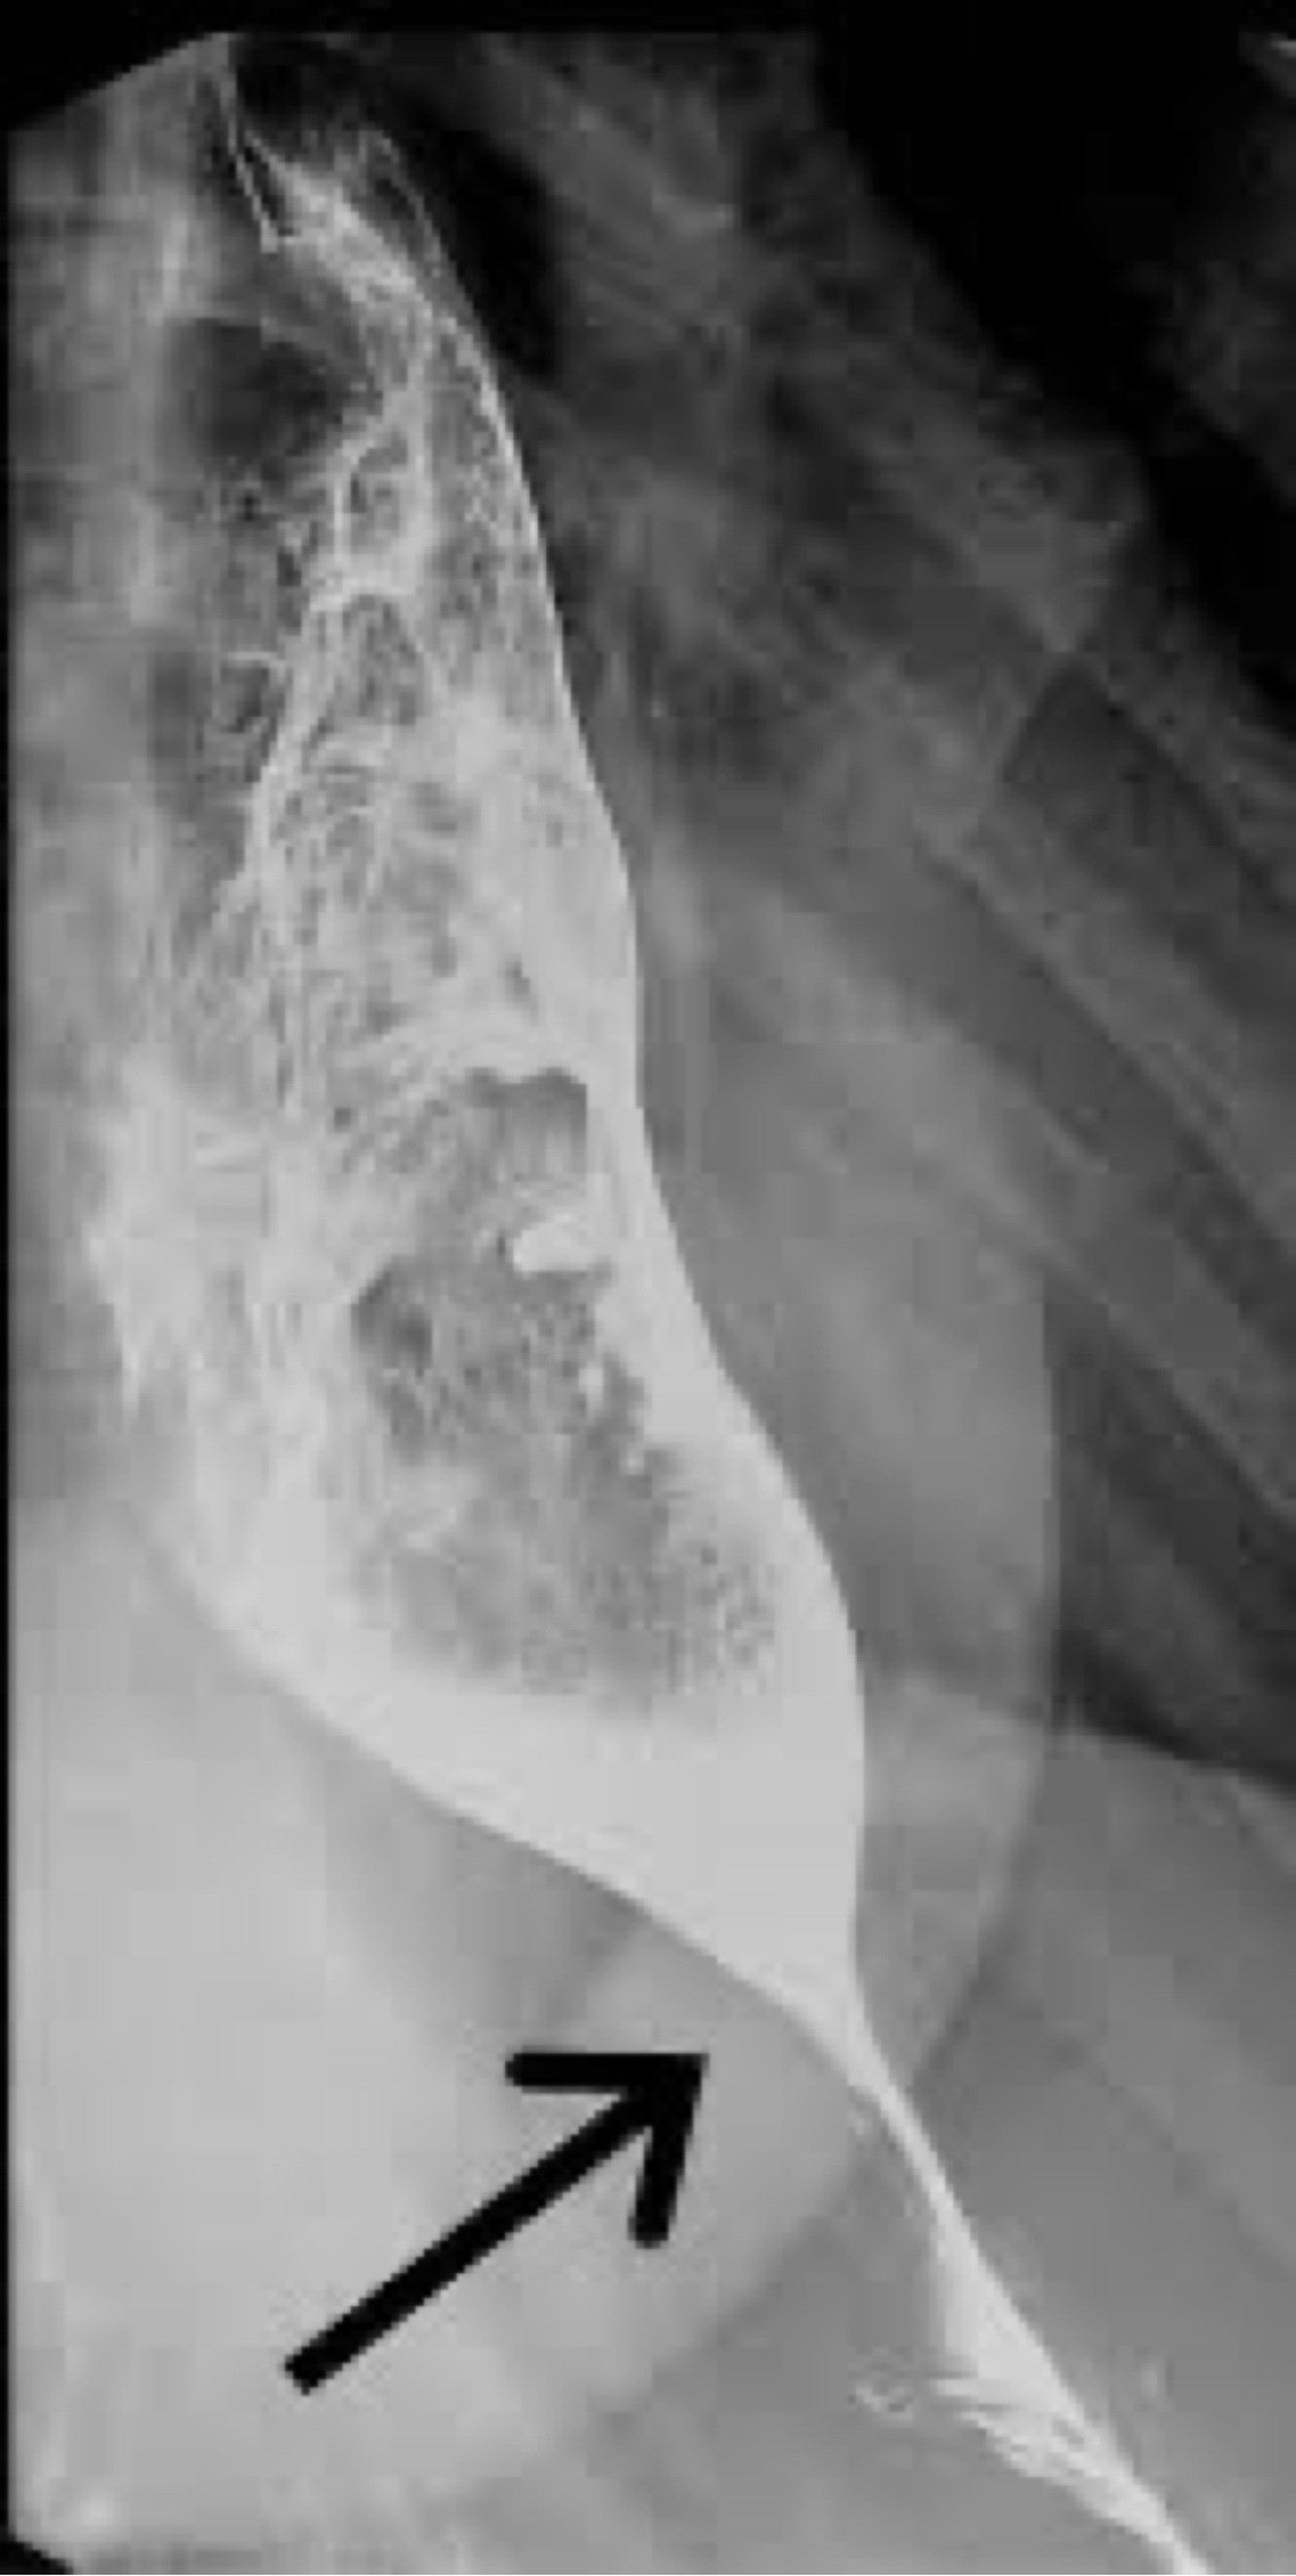

What disease has an abrupt cutoff x- ray?

A

Volvulus